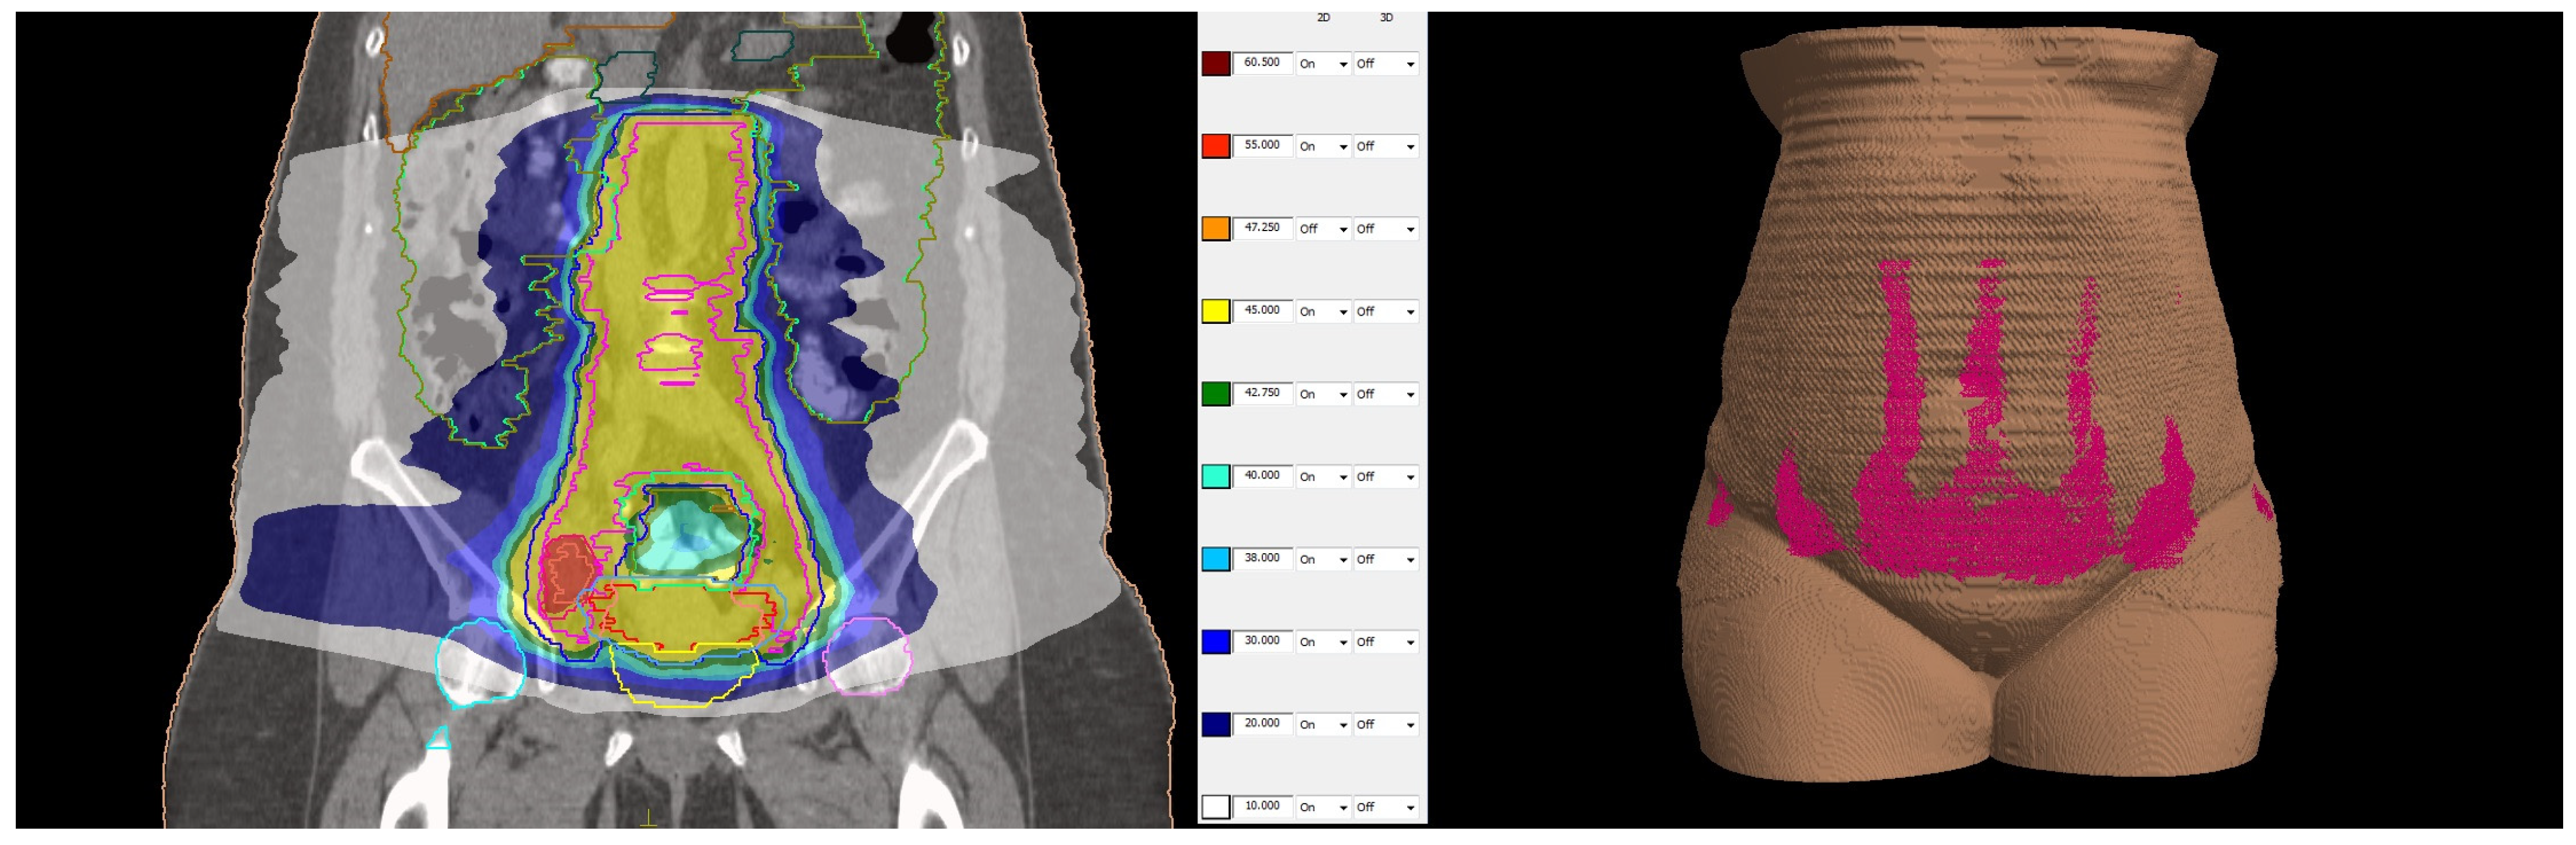

The first fraction of EBT was scheduled for the last day of EBRT to decrease the overall treatment time. The verification that the position of the uterus was appropriate for the 45° tandem was performed by installing a urethral catheter with 200 mL saline infusion and acquiring a cone beam CT image. The patient was positioned lying on a vacuum bag on the operating table and was given short-acting intravenous anesthesia. The insertion of the applicator was performed by a gynecologic oncologist under transabdominal ultrasound guidance. The 45° tandem was inserted to a depth of 4 cm with cervical stopper device and the ovoids were 25 mm in diameter. The applicator was locked to the baseplate by the clamp. When no pain was reported by the patient, she was transported to the CT room for a pelvis CT scan with a 2 mm slice thickness. Images were transferred to the Brachycare TPS, and meanwhile the bladder was emptied for patient’s comfort, followed by patient transfer to the treatment room. Defined OARs were bowel, rectum, bladder, and sigmoid. The target volumes were the CTV high risk covering the whole cervix and CTV intermediate risk, generated with 10 mm margins in lateral and craniocaudal directions and 5 mm in the anteroposterior direction, avoiding the OARs. The prescribed dose per fraction was 7 Gy to the CTV high risk (Figure 5) and the doses in OARs are represented in Table 1.

Figure 5.

Dose distribution: prescribed dose per fraction—7 Gy (red isoline)—covers more than 90% of the CTV high risk; 50% of the prescribed dose per fraction—3.5 Gy (blue isoline)—covers more than 99% of the CTV intermediate risk. The dose on the skin surface was 0 Gy from EBT.